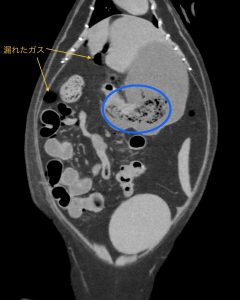

CT検査でも同様の所見があり、胃の出口(青丸)から大腸まで手繰られていました。(オレンジ四角)